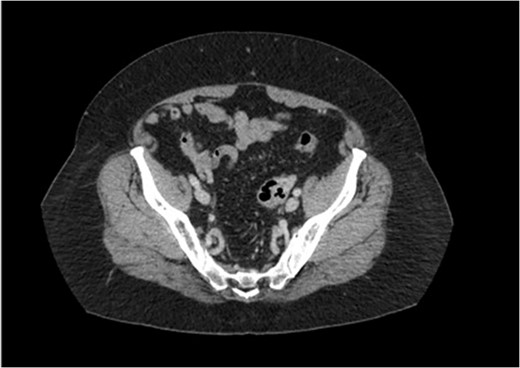

Two weeks later the patient was taken to the operating room for a hand-assisted laparoscopic colon resection and left oophorectomy. Intraoperatively, there were adhesions between the sigmoid colon and left anterolateral pelvic sidewall. Figure 3 shows the inflamed left ovary and fallopian tube adjacent to the sigmoid colon. The left ovary and a small portion of the left fallopian tube were dissected, and then resected en bloc with the sigmoid colon. Figure 4 depicts the uterus status post-resection. An end-to-end anastomosis was performed to the inraperitoneal rectum. The patient had an uncomplicated hospital course and was discharged home on post-operative Day number 2. One month later, the patient was doing well with normal bowel function, resolution of her UTI’s and resolved abdominal pain.

Intra-operative findings of the colo-ovarian fistula including grossly inflamed left ovary and fallopian tube.